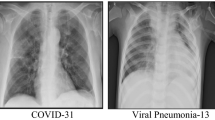

Classical handcrafted feature engineering-based approaches have also proven their competence for COVID-19 detection. Panetta et al.20 proposed a novel shape-dependent Fibonacci-p patterns-based feature descriptor for COVID-19 detection. In another work, Chandra et al.21 first extracted the gray-level cooccurrence matrix (GLCM) and histogram oriented gradient (HOG) based features and then used the binary grey wolf optimizer (BGWO) based feature selection technique to select the near-optimal feature set. Finally, a bi-stage majority voting-aided ensemble mechanism was utilised with the seven different machine learning-based classifiers. The authors classifies normal and abnormal images quite successfully, but the model performance was not good while classifying infected samples into pneumonia and COVID-19 cases. One of the possible reasons for such a behaviour might be related to a recent medical research findings22 where the authors state “In some cases, definite discrimination of the two (COVID-19 and pneumonia) entities might be impossible solely based on the imaging, however, some radiologic features may suggest one diagnosis over the other”.